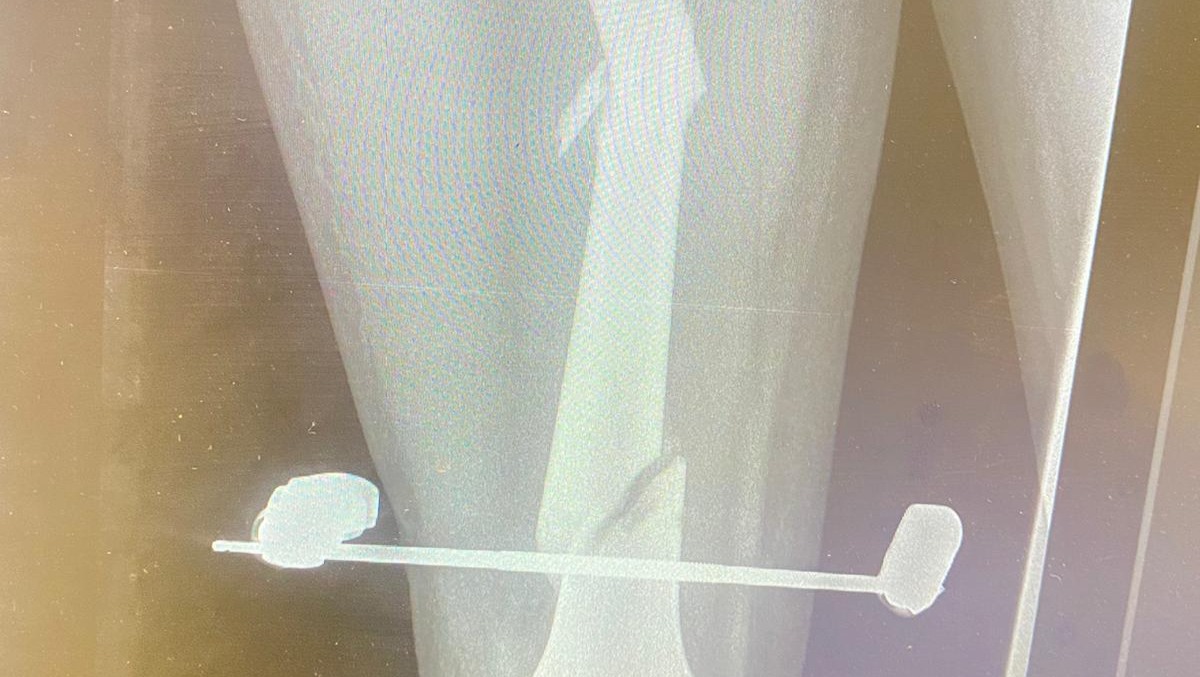

The External Fixation..

An X-ray Of The External Fixation..

The surgery he did in February was because his leg got infected from the inside. And the last surgery he did in April was for the second broken bone, the doctors had put internal pins in the bone.